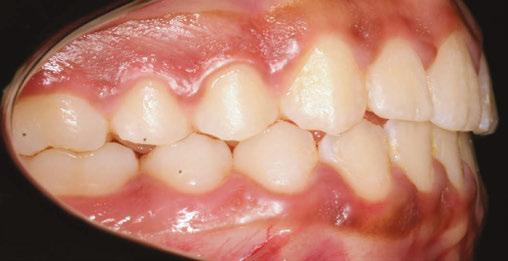

Figure 3: Initial right buccal

This case involves a 13-year-old female patient with a complex malocclusion that includes multiple dental and skeletal issues. During the initial consultation, clinical evaluation showed severe maxillary crowding along with generalized spacing in the mandibular arch. The patient’s occlusal relationships were asymmetric, with a Class I molar relationship on the right side and a Class II molar relationship on the left. Notably, an anterior crossbite was observed, further complicated by a narrow, V-shaped maxillary arch — a common presentation that often exacerbates anterior-posterior discrepancies and limits functional occlusion. The patient also demonstrated poor oral hygiene, which is a key indicator of an indirect bonding system that does not reduce excess flash. ODB is superior in flash reduction, by being able to remove excess adhesive from three sides of the bracket instead of competitors who only remove adhesive from one side of the bracket. The presence of adhesive around brackets contributes to surface roughness which leads to plaque accumulation.1 Flash reduction will be very important for every patient’s orthodontic success (Figures 1-3).